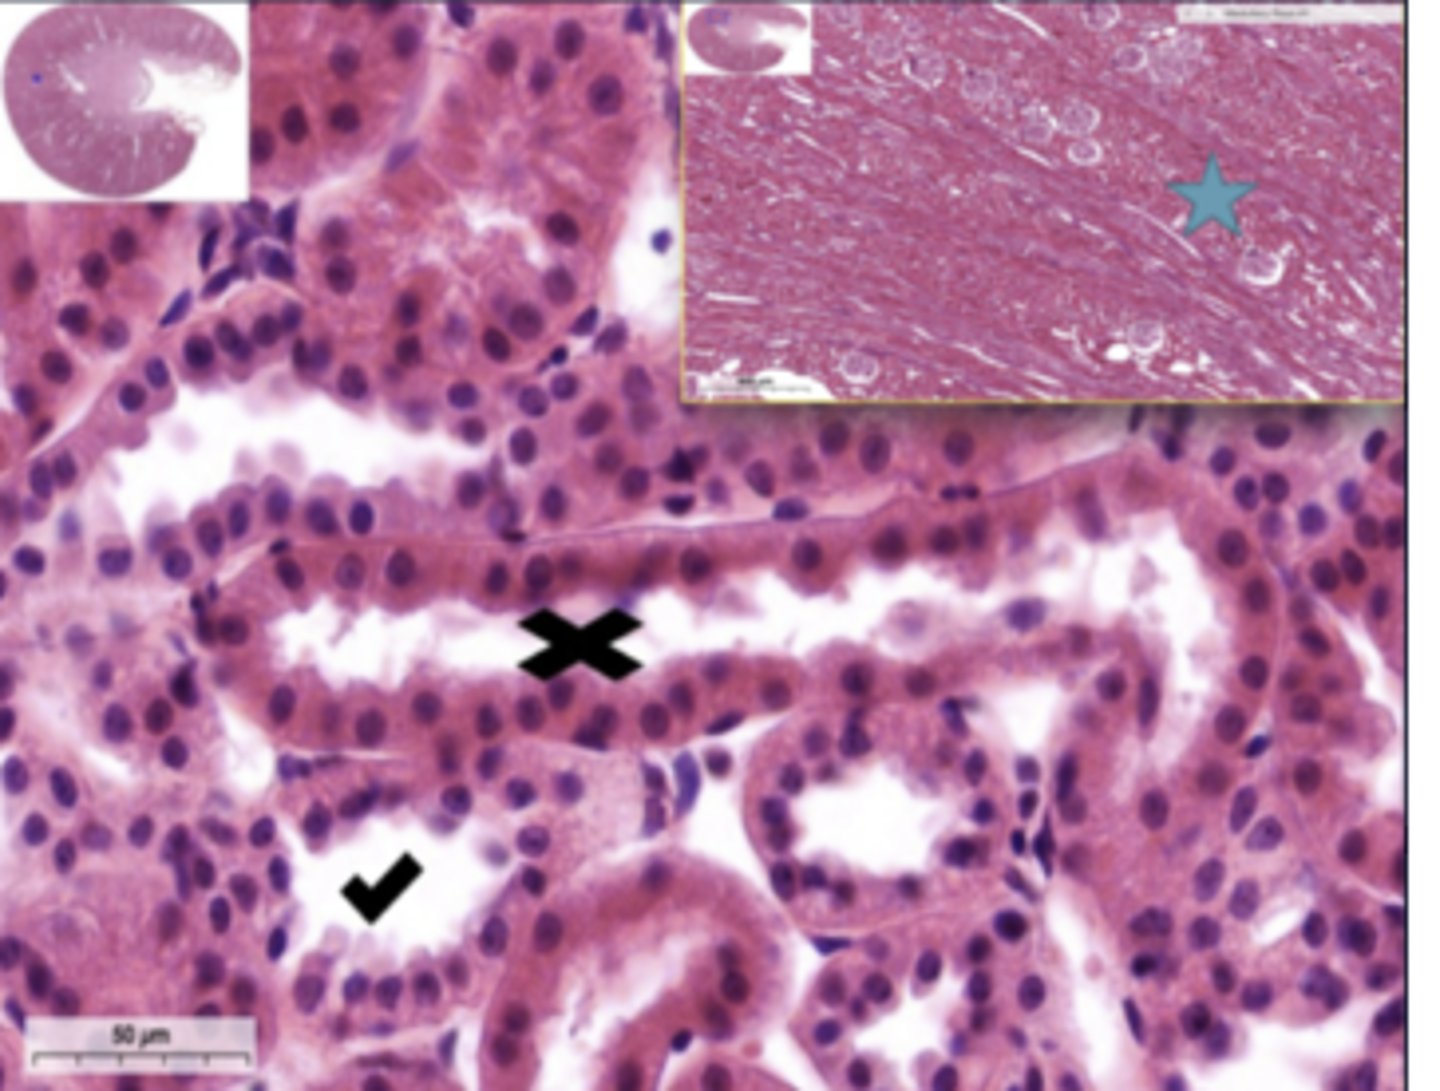

thin loop of henle

cortical labyrinth

X - proximal convoluted tubule

Hassall's corpuscle??

central arteriole